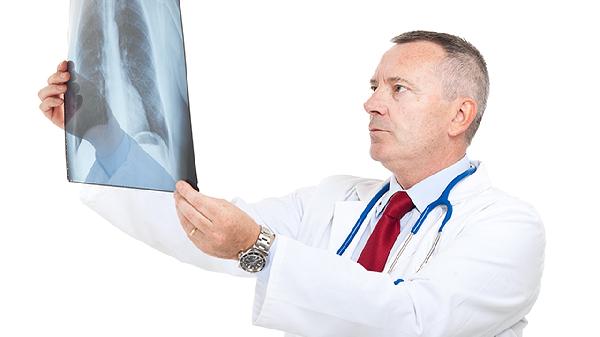

什么是阻塞性肺气肿

阻塞性肺气肿是指细支气管因炎性变化所引来的通气阻塞,简称“肺气肿”,阻塞性肺气肿发病缓慢,病情轻重不同,以咳嗽、咳痰为主要症状,并有气急或胸闷,为了预防阻塞性肺气肿的发生,所以大家要多了解一下阻塞性肺气肿的有关知识。1、阻塞性肺气肿病人在慢性病程中,表现乏力,体重减轻,上腹部疼痛和胀满,如病情严重则有紫绀,头痛,心动过速,嗜睡,精神恍惚,最后可导致自发性气胸...